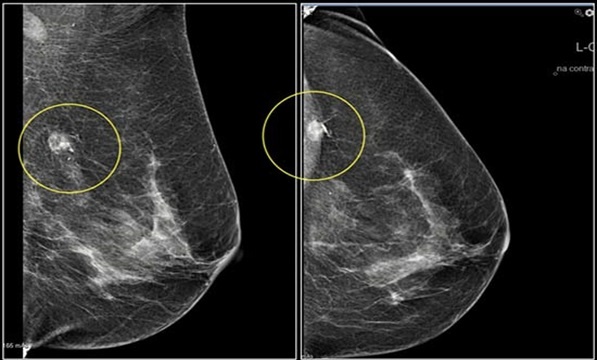

Отток лимфы зависит от локализация опухоли:

- Латеральные квадранты → подмышечные узлы.

- Медиальные квадранты → парастернальные узлы.

- Стадирование рака: Поражение лимфоузлов определяет стадию (N0-N3 по системе TNM).

• Увеличение числа поражённых узлов ухудшает прогноз.